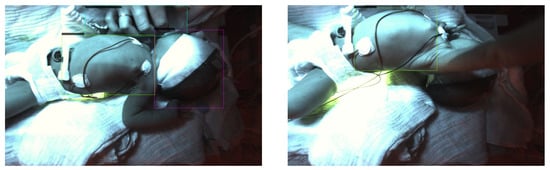

2.4. Measurement Series

2.4.1. Subjects

2.4.2. Training, Validation and Test Datasets